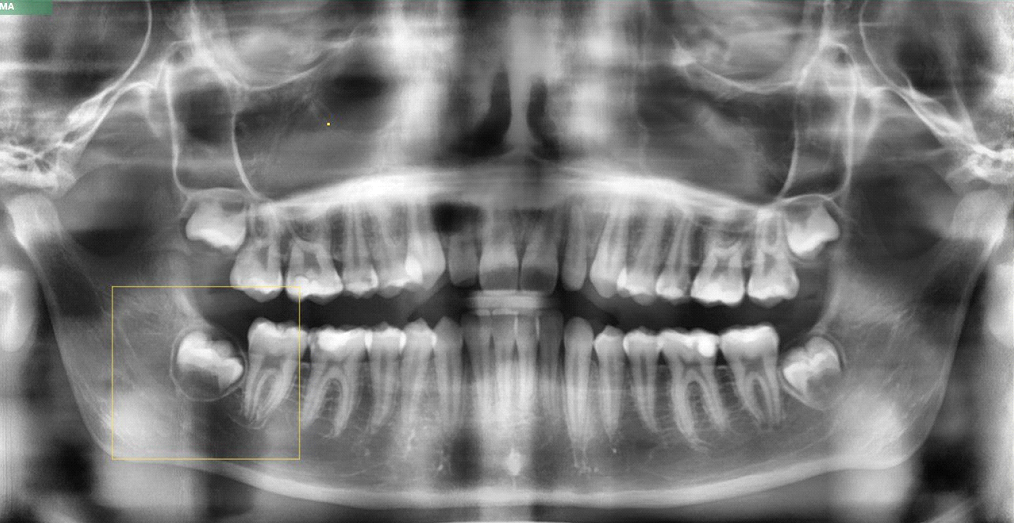

Н 3 кт